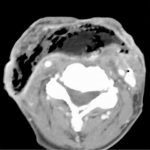

В основе патогенного действия на клетки мозга лежат быстро наступающие изменения в составе крови или так называемые системные эффекты курения [3]. Уже через семь секунд после вдыхания табачного дыма никотин достигает клеток мозга, оказывая на них специфическое действие. Под его влиянием, а также под действием окиси углерода и других веществ (всего в дыме содержится около 3400 соединений [4]) повышается артериальное давление, увеличивается частота сердечных сокращений, концентрация катехоламинов и свободных жирных кислот. Курение может увеличивать свертываемость крови, воздействуя на агрегацию эритроцитов, показатель гематокрита, вязкость, содержание фибриногена, гемоглобина. Нарушаются функция и активность кровяных пластинок [5]. У мужчин нарушение гемореологических свойств крови связано главным образом с вязкостью, которая в свою очередь может быть причиной повышения уровня фибриногена. У женщин эти нарушения преимущественно связаны с увеличением содержания гемоглобина. Указанные изменения гемореологических показателей свидетельствуют о повышении риска кардиоваскулярных заболеваний у курильщиков, ухудшении кровотока и микроциркуляции [6]. Никотин влияет на разные уровни центральной нервной системы, вегетативные ее образования, в связи с чем нарушаются сосудистый тонус и способность адаптации сосудов к другим факторам [7].

При курении существенно снижается локальный мозговой кровоток [11]. Возрастает риск закупорки магистральных сосудов головы. В них могут формироваться атеросклеротические бляшки, суживаться просвет сосудов, ухудшая условия кровоснабжения мозга. Нарушается деятельность сердца. Эти изменения в сердечно-сосудистой системе способствуют развитию как хронических (начальные проявления недостаточности кровоснабжения мозга, дисциркуляторная энцефалопатия, сосудистая деменция), так и острых (преходящие нарушения мозгового кровообращения, малый инсульт, ишемический и геморрагический инсульты) цереброваскулярных поражений.